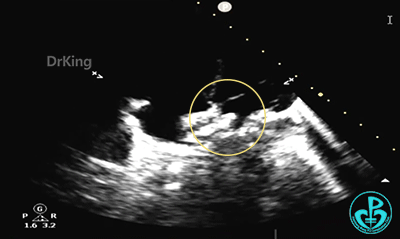

心脏位置及连接正常。各房室腔无明显增大,左室收缩活动可。主动脉三叶瓣,活动可。左右冠状动脉开口可见。肺动脉稍宽,瓣膜开放活动可。房室开放活动可;三尖轻度反流,反流速2.0m/s。房间隔缺损约5.4mm×5.2mm(继发型),近主动脉根部,缺损周围组织较薄软,距上腔静脉12.2mm,距右上肺静脉15.2mm,距二尖瓣环7.4mm,缺损下缘22.6mm,左向右分流为主,偶见右向左分流。沿室间隔未显示明显分流。

锁定后,主动脉短轴切面显示封堵器呈Y字型抱住主动脉根部。

主动脉短轴切面显示封堵器呈Y字型抱住主动脉根部,夹持稳定。